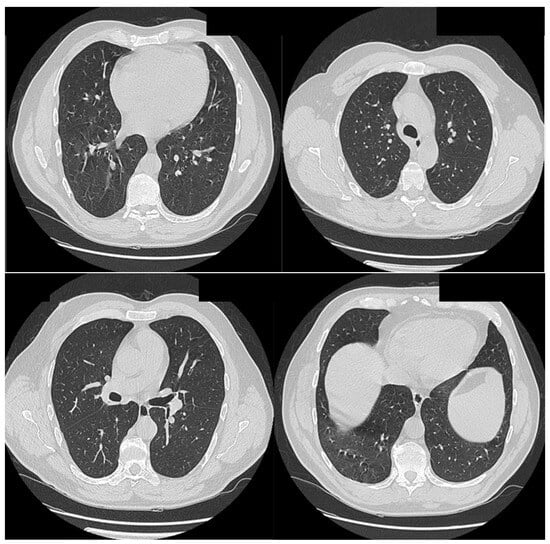

2.3. Case 3